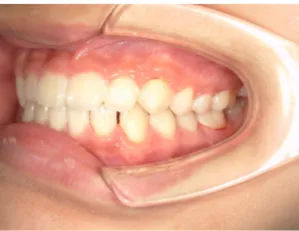

治療中⑥小4(10y2m):モノブロック装置継続中 上下正中改善中

治療中⑦小5(11y3m):モノブロック装置継続中

治療後⑧小6(12y3m):モノブロック装置継続中

治療後⑨中2(13y11m):モノブロック装置継続中

咬み合せも安定していて、口元の突出・口唇閉鎖不全も改善

*レントゲンや歯の萌出状況などから成長が終了していると考えられるため、現在残っている隙間や上下正中の不一致を改善するためマルチブラケット法へ移行するか検討中です。